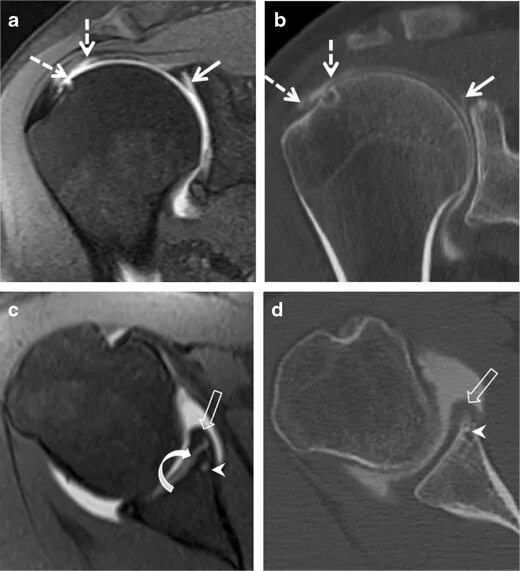

Мрт суставов кемерово